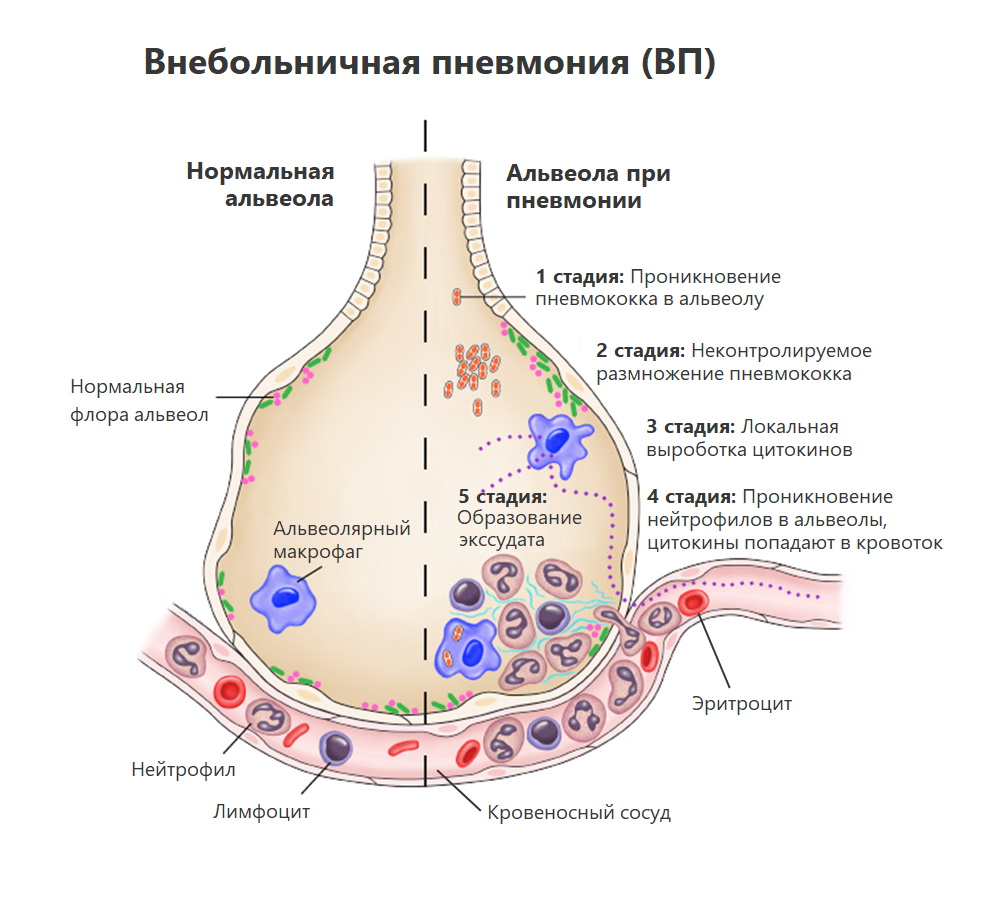

Фотографии бактерий, вызывающих бактериальные пневмонии у животных